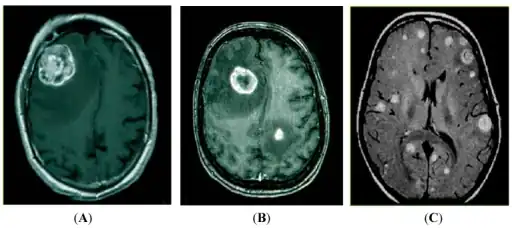

Brain imaging (neuroimaging such as CT or MRI) is needed to determine the presence of brain metastases.[5] In particular, contrast-enhanced MRI is the best method of diagnosing brain metastases, though detection is primarily done by CT.[9] Biopsy is often recommended to confirm diagnosis.[5]

In brain metastasis due to malignant melanoma, MRI imaging showed high T1 and low T2 intensity due to the deposition of melanin in the brain. In susceptibility weighted imaging (SWI), it usually shows abnormal SWI hypointensity in larger proportion than brain metastasis caused by breast carcinoma.[11]